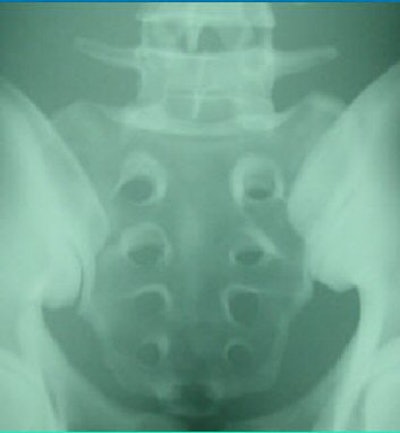

| The image above is from a CR system; the image below is from a DR system before standardizing the images. The pelvis phantom was imaged at a surface-to-image distance (SID) of 40 inches (100 cm), 80 kVp, and 50 mAs. Image courtesy of Larry Frederick and David Piazzo. |